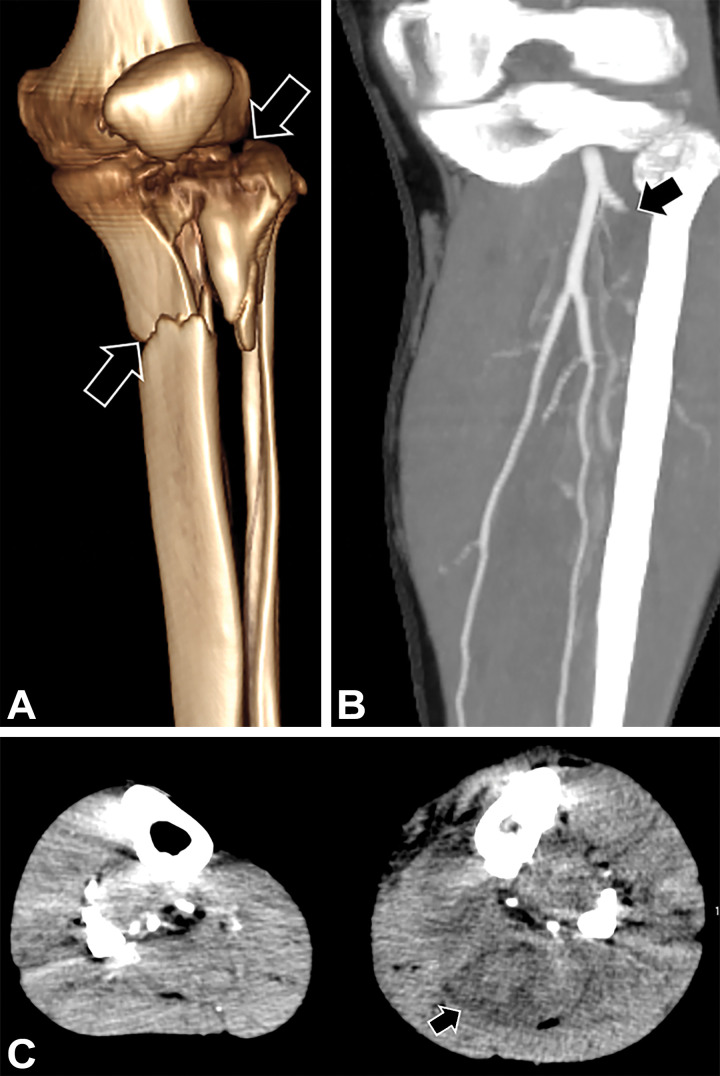

Figure 5:

Crush injury to the distal left leg and clinical signs of compartment syndrome in a 39-year-old man. (A) 3D VR image shows a comminuted proximal tibial fracture (arrows). (B) Coned-down coronal MIP CTA image of the below-the-knee arterial runoff shows occlusion of the left anterior tibial artery (arrow) shortly beyond its origin. (C) Axial MIP CTA image of the lower legs shows enlarged edematous calf musculature (arrow) in the left lower extremity, compatible with clinically suspected compartment syndrome. Compartment pressures measured approximately 80 mm Hg. Four-compartment fasciotomy was performed.